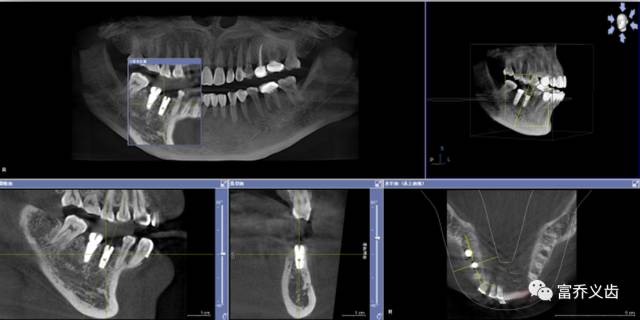

手术后CBCT以及曲面断层片